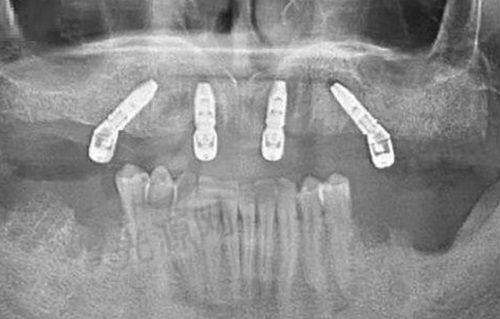

在种植牙技术方面,麦芽口腔拥有智能数字化精细种植牙、即刻用种植、前牙美学种植、ALL - ON - 4种植、微创舒适种植等多种精良技术。其中,智能数字化精细种牙技术尤为突出,它能够实现三维立体清晰成像,一次可以提取近30项口腔数据,辅助医生进行精细诊断和智能数字化方案设计,使种植过程更加精细正确,减少术中创伤,术后牙齿也更加稳固。在设备方面,麦芽口腔引进了德国卡瓦CT(误差<0.1mm)、iTero口扫仪(5分钟生成3D牙模)等精良设备,大大提高了诊断的正确性和治疗的安心性。